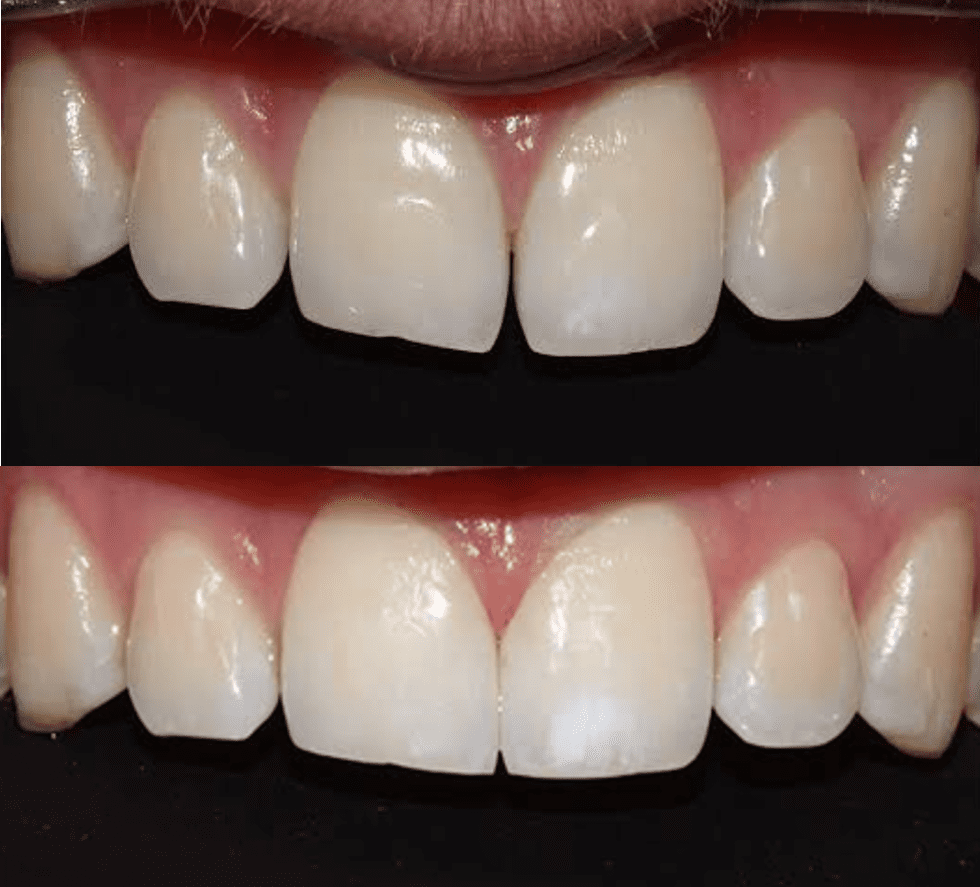

• Smile designing and esthetic correction

• Ceramic Veneers

• Indirect Esthetic Restorations